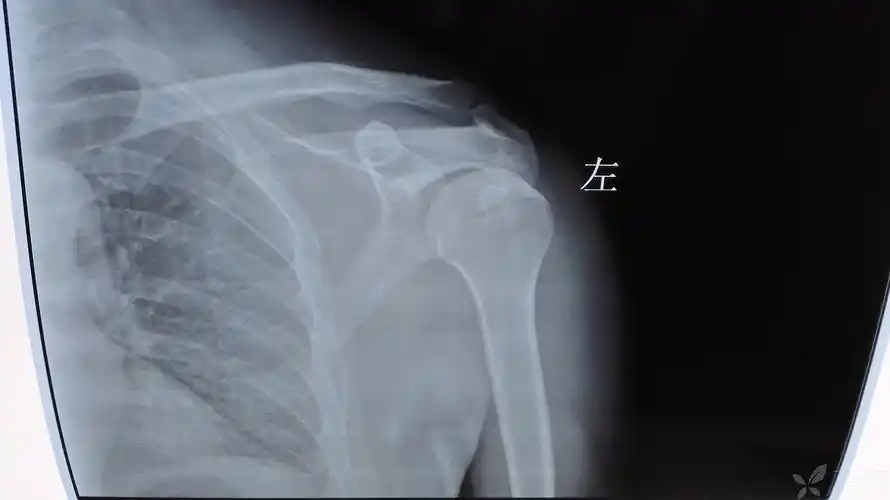

18 高绪仁的肩锁关节脱位损伤患者x片.jpg

肩部骨折会有局限性疼痛,可导致肢体功能完全丧失,并发症有休克